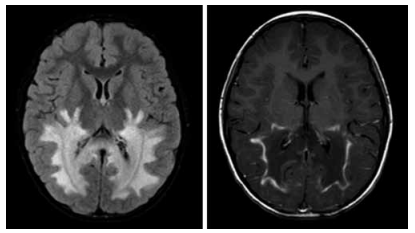

Menino de 6 anos de idade apresenta quadro progressivo de comprometimento cognitivo e espasticidade. As imagens por ressonância magnética do crânio FLAIR e T1 com contraste, respectivamente, demonstram as alterações a seguir.